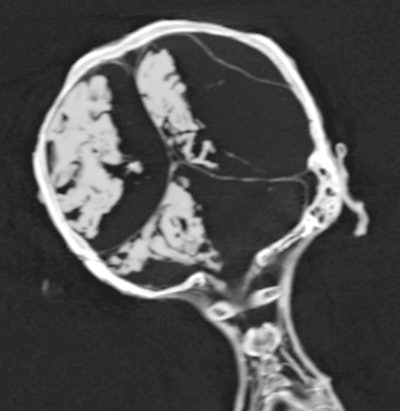

3D CT images of the mummy documented the tilted head position, while 2D CT image showed intactness of the skull base, without any attempt of brain removal. The desiccated shrunken brain is seen in the CT images shifted to the right side of the cranial cavity. No resin or other embalming materials are seen within the cranial cavity.